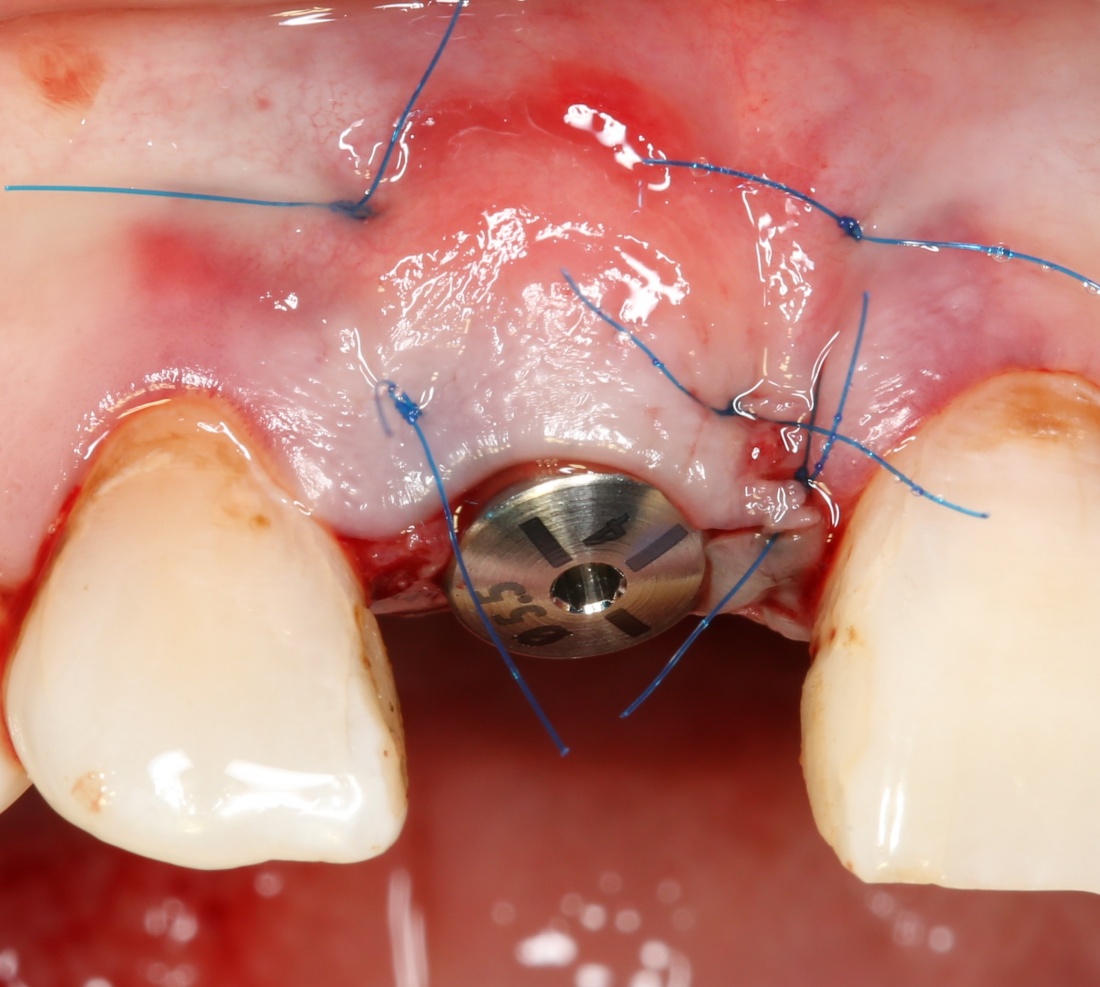

Графт адаптируется (с помощью скальпеля), устанавливается в нужное положение. Для этого, опять же, очень удобно использовать аналоги имплантов из имплантологического набора (в крайнем случае, остеотомы или пины параллельности):

Напомню, нет необходимости заполнять графтом всю лунку. Тем более — полость удаленной кисты или гранулемы. Поэтому 100 мг вполне хватает, чтобы аугментировать лунку любого объема.

Благодаря своим свойствам. Bio-Oss Collagen не забивается в подготовленную лунку импланта, не съезжает и не сползает при его установке:

Вот, собственно, и всё. Далее, наш биоматериал ведет себя совершенно также, как и обычный Bio-Oss — он быстро пропитывается кровью и отлично удерживается на месте:

В данном случае мы планировали закончить этап немедленной установкой временной коронки, этим займется ортопед через полчаса после установки импланта. Пока же, я закрываю имплантат формирователем десны и накладываю швы: